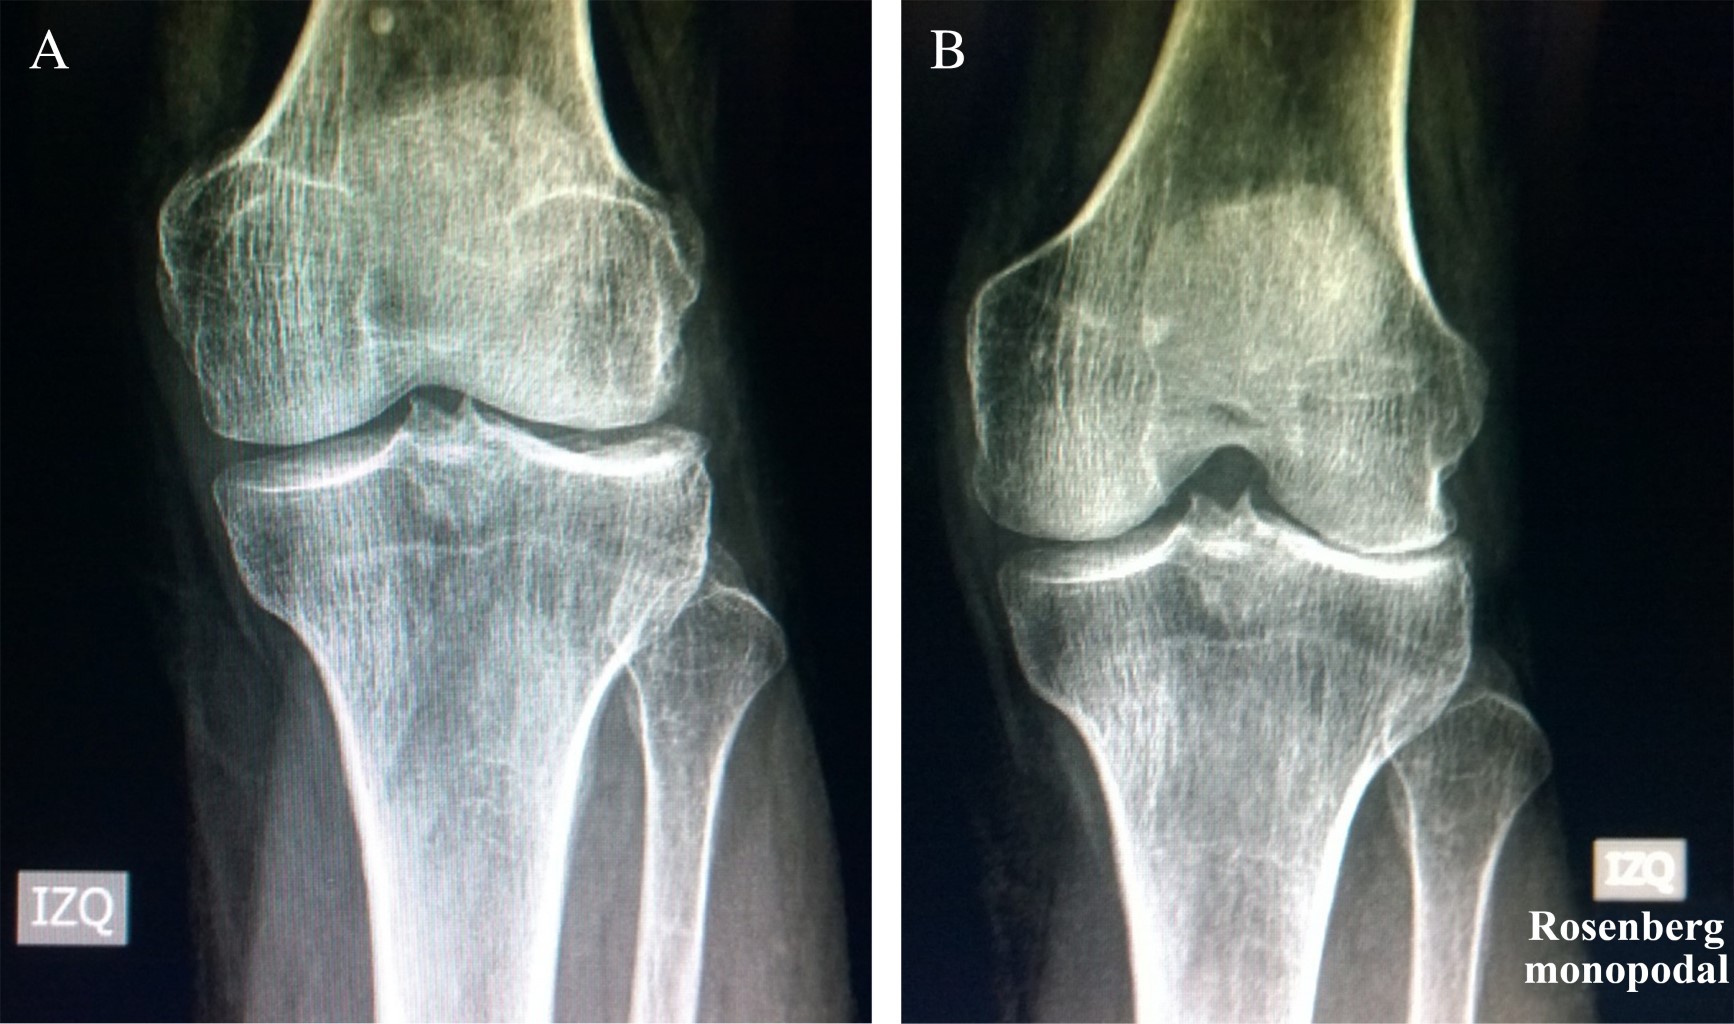

Radiografías con carga anteroposterior y lateral, Rosenberg o schuss (Figura 1).10 Radiografías axiales de patela en 20 grados. Telerradiografía de extremidades inferiores.

Todas estas radiografías nos permiten tener una respuesta bastante certera de la condición de la rodilla y de su alineamiento.